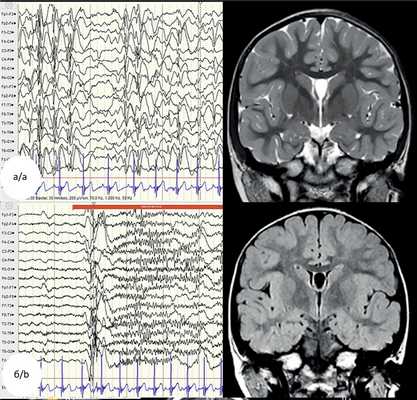

Рис. 6 (а—б). Пример резекции фокальной кортикальной дисплазии I типа лобно-центральной области слева.

Девочка, 5 лет, праворукая, болеющая эпилепсией с 8 мес. На момент операции — очень частые и резистентные к антиэпилептическому лечению эпилептические спазмы и асимметричные тонические приступы, а также начальные признаки задержки в развитии. Учитывая обширность изменений в лобно-центральных отделах доминантного полушария и неопределенность их границ, операцию ограничили частичной резекцией мальформации в пределах премоторной коры при ориентировке в основном по данным магнитоэнцефалографии и интраоперационной электрокортикографии. После непродолжительного и незначительного уменьшения частоты приступов они возобновились и сохранялись вплоть до последнего осмотра спустя 14 месяцев. Исход IVB. а — слева — интериктальная электроэнцефалография, мультирегиональная эпилептиформная активность (нередко — вплоть до гипсаритмии); б — слева — иктальная электроэнцефалография. Тонический приступ с предшествующей ему редукцией и десинхронизацией активности; диффузный разряд пик-волн, совпадающий с началом клинических проявлений, и последующая диффузная низкоамплитудная быстроволновая активность с включением пиков (fast activity). Справа — дооперационные магнитно-резонансные томограммы в режимах T2 и T2-FLAIR, на которых в коре средней и нижней лобных извилин слева отмечается усиление сигнала и нечеткость ее границ с белым веществом, а также линейный участок повышенного сигнала, распространяющийся от левой прецентральной извилины до тела бокового желудочка (стрелка) и симулирующий «трансмантийный тяж», совпадающий с топографией магнитоэнцефалографических источников инициальных разрядов длительных последовательностей, в том числе иктальных (см. также в).

Рис. 6 (в—г). Пример резекции фокальной кортикальной дисплазии I типа лобно-центральной области слева.

в — результаты локализации источников эпилептиформной активности во сне по данным магнитоэнцефалографии. Зелеными точками отмечены источники интериктальных разрядов как одиночных, так и входящих в состав длительных последовательностей, красными — источники начала длительных последовательностей разрядов, на фоне которых у пациентки возникли два тонических приступа. Следует отметить, что эта же зона первой включалась в генерацию многочисленных и длительных интериктальных последовательностей без клинических проявлений; г — слева — вид операционной раны к моменту завершения субпиального опорожнения коры средней и медиальной лобных извилин кпереди от прецентральной борозды (кора нижней лобной извилины сохранена с учетом доминантности полушария); справа — иммуногистохимический препарат — видны выраженные нарушения корковой архитектоники по смешанному типу (экспрессия NeuN, ×100).

Важно указать также, что ни один из разнообразных патологических паттернов ЭЭГ, как интериктальной, так и иктальной, не может считаться специфическим для ФКД, не говоря уж о том, чтобы предположить их морфологический тип. Одним из немногих более или менее типичных признаков ФКД II типа в интериктальной ЭЭГ считаются вспышки ритмической активности на фоне локального и нерегулярного замедления биоэлектрической активности (см. рис. 5) [19, 20], но такой паттерн встречается далеко не у всех. Ранее мы сообщали о попытке сопоставить находки в ЭЭГ с морфологией ФКД [21]. В случаях со II типом КД начало приступов лишь в 40% совпало с локальной ритмической активностью, порой с предшествующим электродекрементом, а у детей с I типом дисплазии (несколько более частым и, что важнее, синхронным, с манифестацией приступов) оказалось только диффузное уплощение ритмики (см. рис. 6). Зоны интериктальной и приступной активности совпали менее чем у половины.